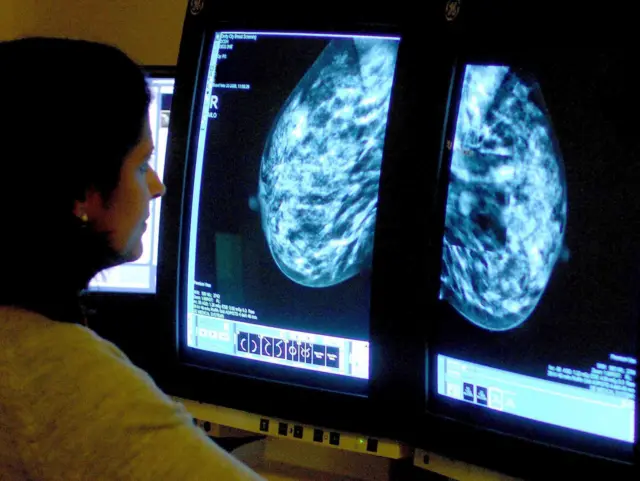

Read MoreThe trust which runs Lincolnshire's hospitals is one of just two in the country to take part in a groundbreaking new trial using artificial intelligence (AI) to support breast screening.

Image source, Press AssociationCurrently all images produced during mammograms are reviewed by two members of the breast screening team.

But it's hoped the new assessment tool will revolutionise the way scans are read and analysed in the future.

Simon Harris, from the East Midlands Radiology Consortium, said: "Artificial intelligence is very good at pattern recognition. It looks at a mammogram image and it looks at certain markers or signs that are in there which might be something of interest.

"It's not very good at creative thinking in the way a human would be, but it is very good at spotting differences in images."

Consultant mammographer Bernadette Trzcinski says she thinks it'll make a big difference.

"It also means the women we have to recall because we've spotted something on their mammogram which we want to have a further look at, we have more time to spend with those women who are very anxious," she says.